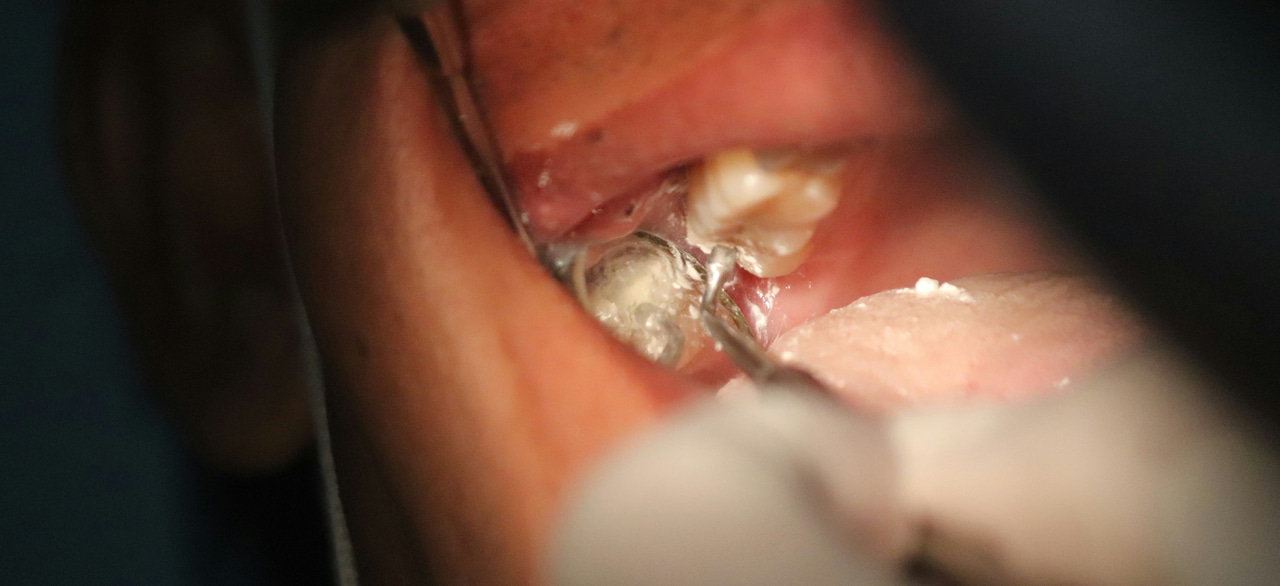

Salivary stones, also called sialoliths or salivary gland stones, are small calcified deposits that form in the salivary glands, most often in the submandibular salivary gland. These stones can block the flow of saliva, which can cause pain and swelling, especially during meals.

2. Larger stones: Sometimes require a doctor to remove the stone through a minor surgical procedure surgery.